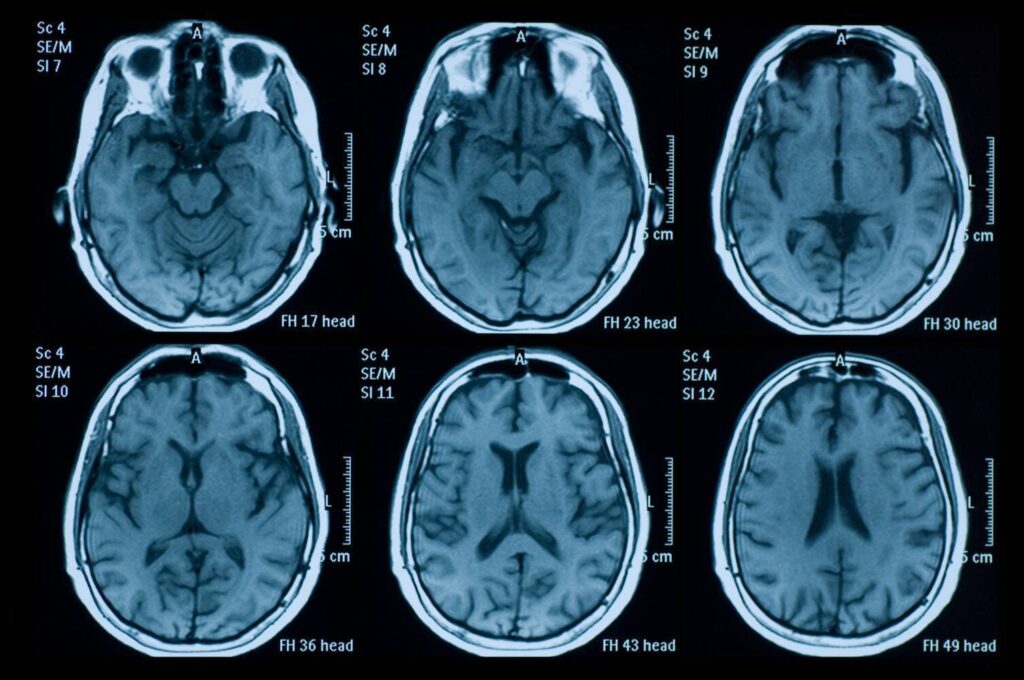

Die Magnetresonanztomographie (MRT) ist bei der MS das bildgebende Mittel der Wahl zur Diagnostik und Verlaufsbeobachtung. Die Entzündungsprozesse werden hier als helle oder dunkle Flecken im Gehirn und Rückenmark sichtbar, die als Läsionen oder Herde bezeichnet werden. Entscheidend ist dabei, dass diese Läsionen das Kriterium der „räumlichen“ und „zeitlichen Dissemination“ erfüllen. Soll heißen: die Flecken sind über mehrere, ganz bestimmte Regionen von Gehirn und Rückenmark verteilt und zu unterschiedlichen Zeitpunkten aufgetreten. Unter Umständen kann hierfür auch Kontrastmittel zum Einsatz kommen, da schwächer ausgeprägte Läsionen – also weniger aktive Entzündungsbereiche – so besser dargestellt werden können.